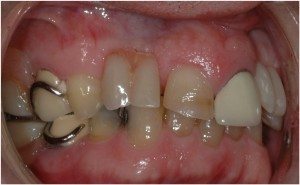

Cosmetic dentistry involves the Smile. It can be something as simple as smoothing the edges of the front teeth or whitening to changing the shape of one crooked tooth with bonding; to a full mouth reconstruction. We have extensive experience and training in cosmetic dentistry. There is nothing as rewarding as seeing the joy of a patient as they see an improved Smile for the first time.

Sometimes the best treatment is what we term βInstant Orthodonticsβ, where we are able to correct mal-positioned and mal-colored teeth with beautiful long-lasting porcelain restorations that are stable and quickly provide a long-lasting result.